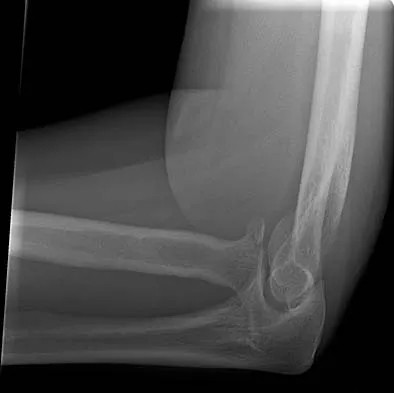

A 78-year-old woman falls onto her nondominant left elbow and sustains the injury shown in Figure 5. What treatment option allows her the shortest recovery time and highest likelihood of good function and range of motion?

Explanation

Total elbow arthroplasty has become the treatment of choice for complex, comminuted distal humeral fractures in patients older than age 70 years. It yields a faster recovery with more predictable functional outcomes, although limitations of lifting weight of more than 5 pounds must be followed to avoid loosening. Kamineni S, Morrey BF: Distal humeral fractures treated with noncustom total elbow replacement. J Bone Joint Surg Am 2004;86:940-947.